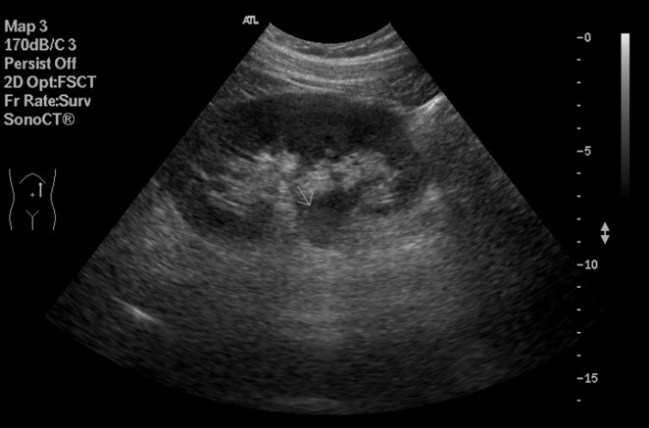

Tumores Renales:

En ecografía la mayoría de los tumores son sólidos.

Ecograficamente pueden ser hipoecogénicos, isoecogénicos, o hiperecogéncios y de gran variedad de formas.

El Doppler presenta una alta sensibilidad para detectar vascularización tumoral.

Doppler